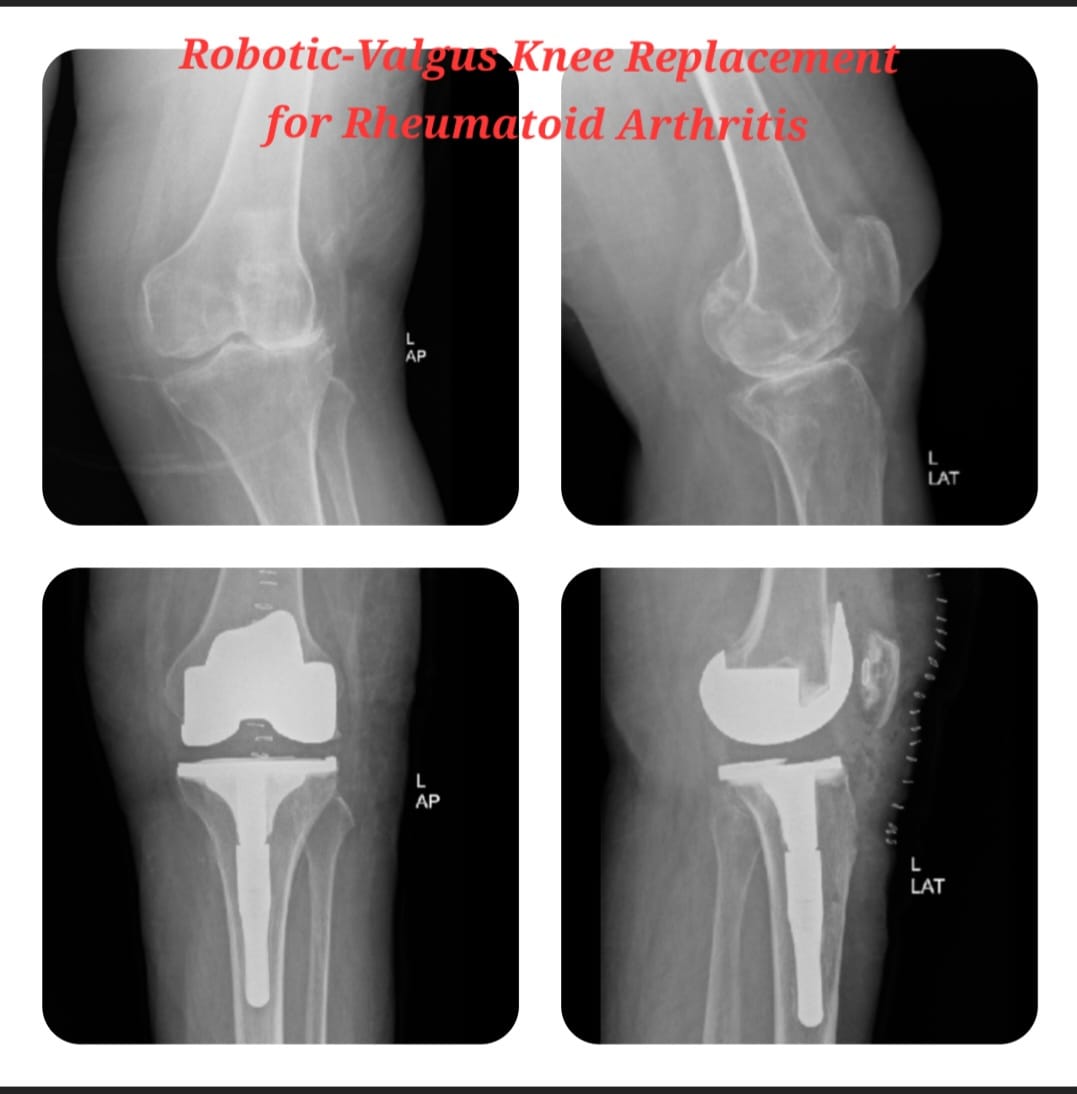

Knee replacement, also known as knee arthroplasty, is a surgical procedure performed to relieve chronic knee pain and restore joint function in patients suffering from advanced arthritis, severe joint damage, or deformities. The procedure involves replacing damaged cartilage and bone surfaces with durable artificial implants that restore smooth knee movement.

Knee arthroplasty is carefully planned based on the patient’s age, activity level, degree of joint damage, and overall health. Modern surgical techniques and advanced implant designs allow improved alignment, stability, and long-lasting outcomes with reduced postoperative discomfort.